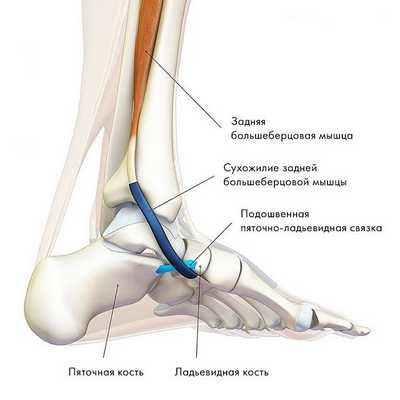

Сухожилие задней большеберцовой мышцы — одно из важнейших сухожилий нижней конечности. Сухожилие — это анатомическое образование, посредством которого мышца прикрепляется к кости. Сухожилие задней большеберцовой мышцы располагается в области внутреннего края стопы. Основной функцией этого сухожилия является поддержание свода стопы и стабилизация стопы при ходьбе.

Сухожилие задней большеберцовой мышцы располагается вдоль внутренней поверхности голеностопного сустава и стопы.

2. Заднее большеберцовое мышечное образование, берущее начало в районе малоберцовой и большеберцовой костей и, с другой стороны, прикрепленное к ладьевидной кости, отвечает за инверсию стопы, ее сгибание в голеностопе и (ключевая функция) стабилизацию ее свода.

Сокращаясь в процессе бега или ходьбы, данная мышца осуществляет блокировку сустава стопы, заставляя ее работать подобно жесткому рычагу. При этом, травмирование, перерастяжение, либо разрыв сухожилия задней большеберцовой мышцы провоцирует развитие такого широко распространенного недуга, как плоскостопие.